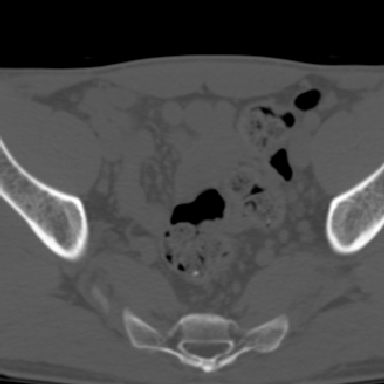

m 30 腰背部不适半年; 清晨时僵硬; 活动症状有所改善

双侧骶髂关节下2/3关节面模糊,毛糙,可见小囊状骨质破坏区.支持强直性脊柱炎.

强直性脊柱炎的早期改变!不仅表现为双侧骶髂关节,第5腰椎与骶椎间的关节突关节也有类似改变。

双侧骶髂关节下2/3关节面模糊,毛糙,髂骨侧可见小囊状骨质破坏区,骶髂关节间隙增宽(软骨破坏期)。支持早期强直性脊柱炎。

双侧骶髂关节下2/3关节面模糊、毛糙,可见小囊状骨质破坏区,呈虫咬状改变,周围可见增生硬化.支持强直性脊柱炎早期表现.

双侧骶髂关节髂骨面硬化,毛糙,小囊变,属于早期强直性脊柱炎